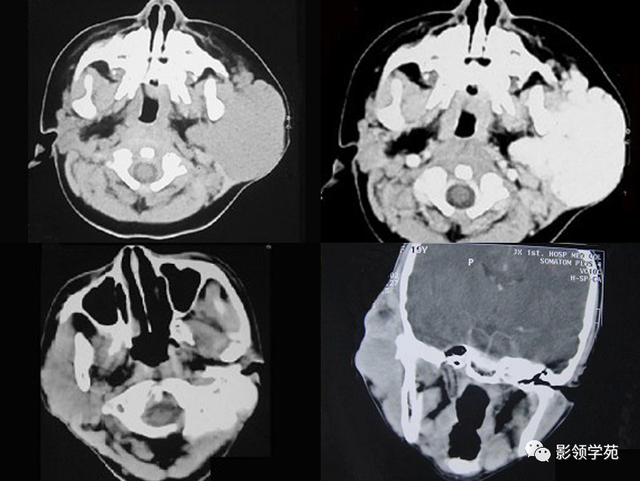

图6 a 、b 、c 囊腺癌 左侧腮腺弥漫性增大,密度增高,边缘无法确定,同侧颈部可见淋投合肿大坏死,胸锁乳突肌受侵占